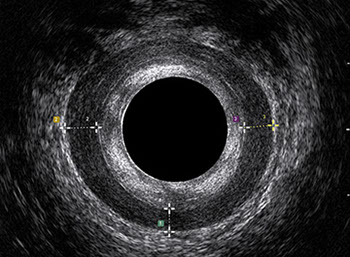

L’ecografia transanale è un esame diagnostico per immagini che consiste nell’introduzione di un trasduttore ad ultrasuoni. Le immagini qualitativamente migliori del canale anale sono ottenute usando un trasduttore rotante, montato in un manipolo rigido, che fornisce un’immagine a 360°. Con le apparecchiature più moderne è anche possibile ottenere immagini tridimensionali.

L’ecografia transanale permette di distinguere la sottomucosa che riveste il canale anale, lo sfintere anale interno, e lo sfintere anale esterno.

Proctal dispone di apparecchiatura per ecografia endoanale 3D con sonda rotante.